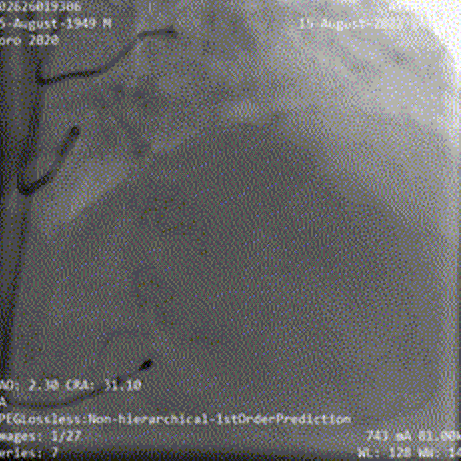

患者弓部较锐利、横位心,TaurusElite输送系统在snare辅助下完成过弓跨瓣后,AV29瓣膜于瓣环平面0mm开始定位释放;

Snare辅助下过弓、跨瓣

瓣膜初始定位